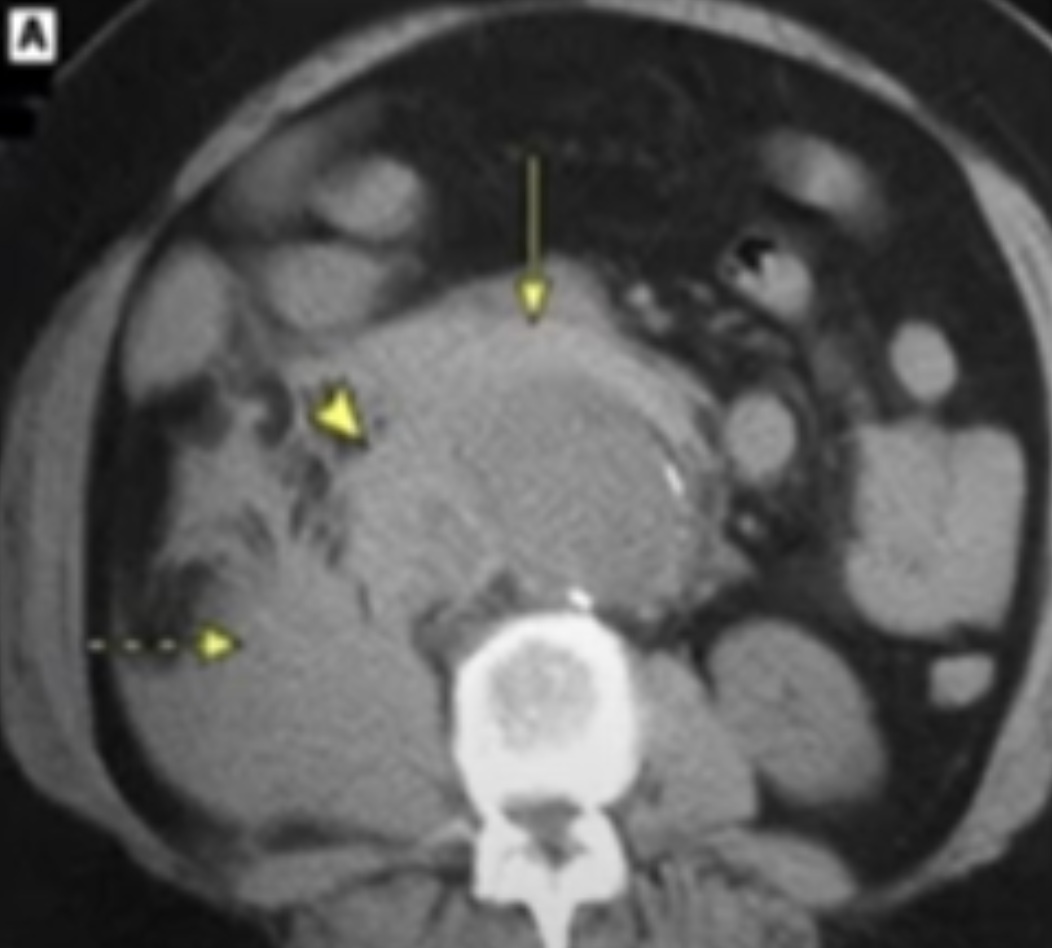

Qual o diagnóstico?

Ruptura de aorta 🩸

(causa de abdome agudo hemorrágico)